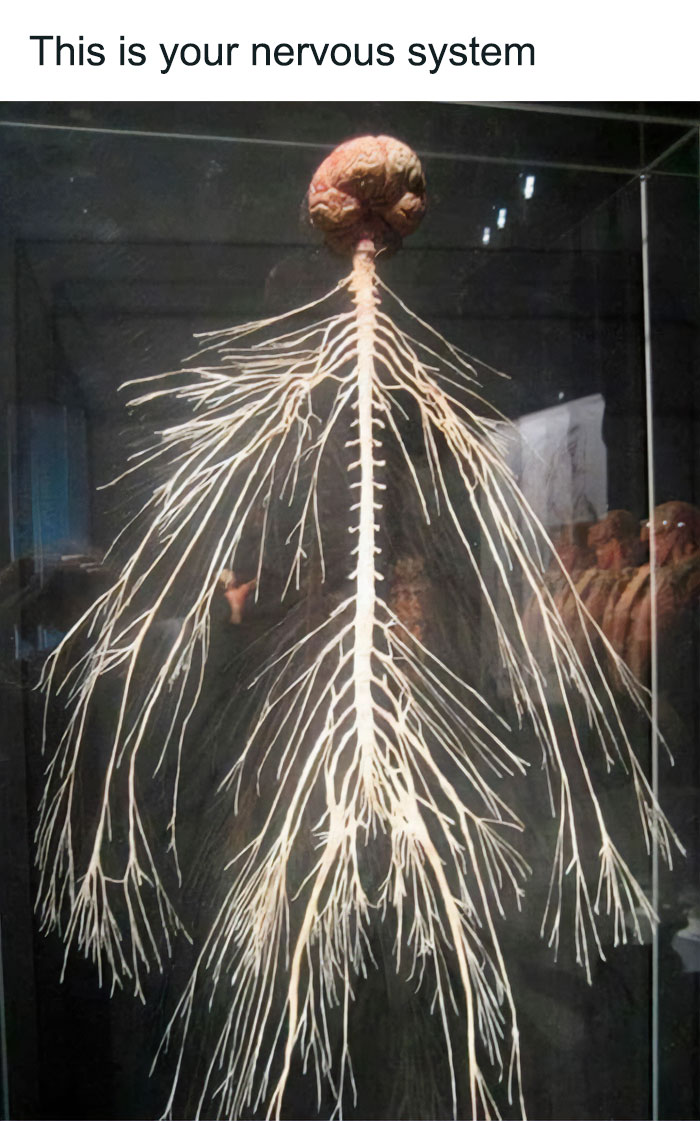

A Dissection Display Of The Entire Peripheral Nervous System